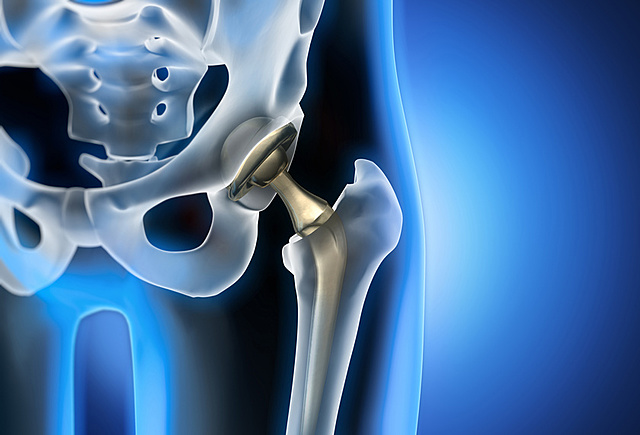

• Reemplazo articular en la Actualidad

Reemplazo articular en la Actualidad

El reemplazo articular es hoy en día un proyecto multidisciplinario donde colaboran cirujanos ortopédicos, bioingenieros, diseñadores de prótesis, estadísticos e informáticos.

El último período del desarrollo de los tratamientos de articulaciones artrósicas todavía es experimental y se orienta hacia la célula cartilaginosa y su capacidad para diferenciarse o regenerarse a partir de una célula precursora, y así tratar de restaurar la función de la articulación enferma.